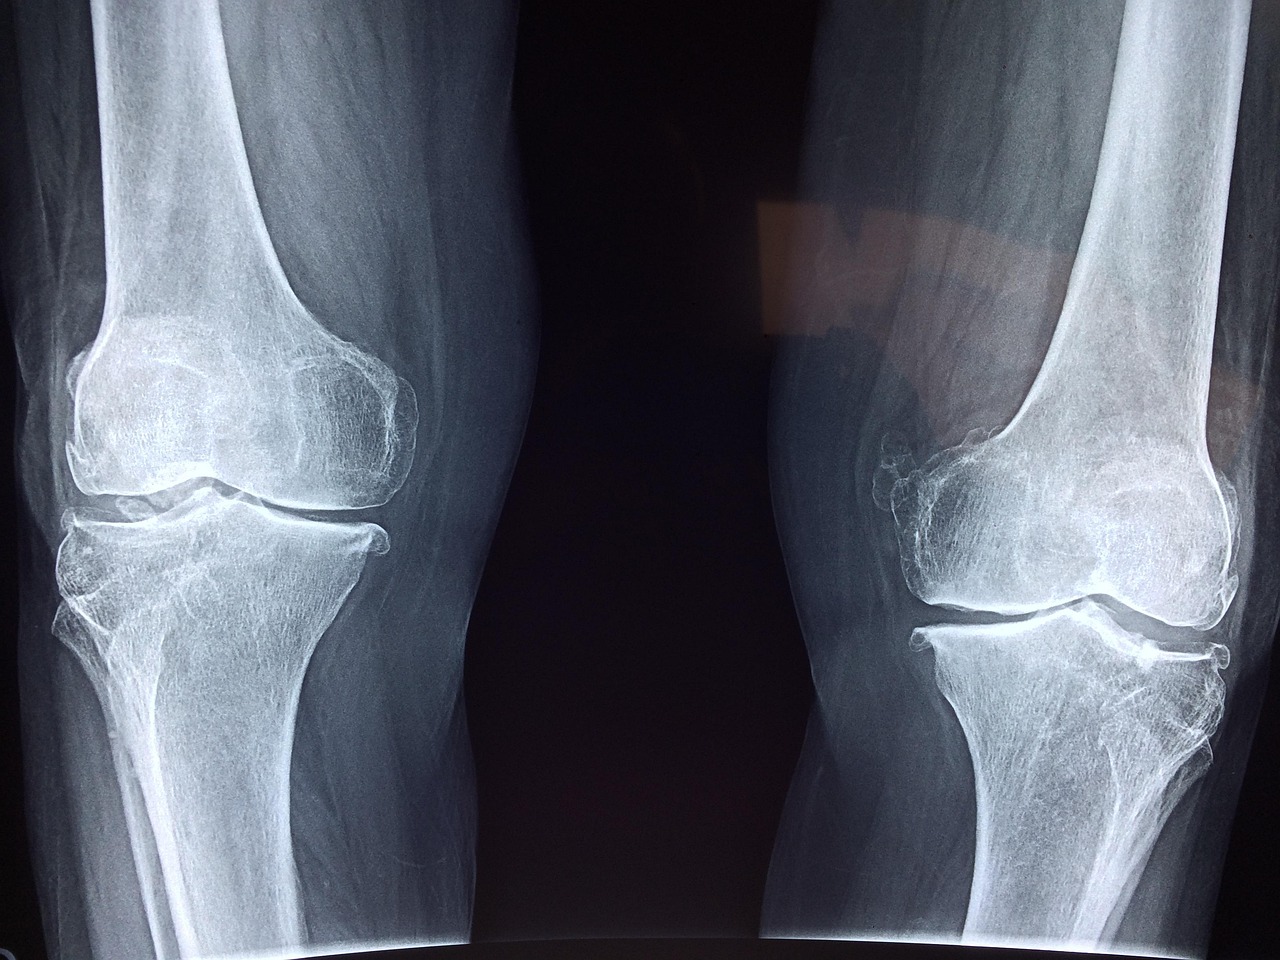

4-1. X-ray

초기 단계에서는 뼈의 괴사가 보이지 않을 수 있지만,

질환이 어느 정도 진행된 경우에는 뼈의 모양이 바뀌거나 함몰된 모습이 나타납니다.